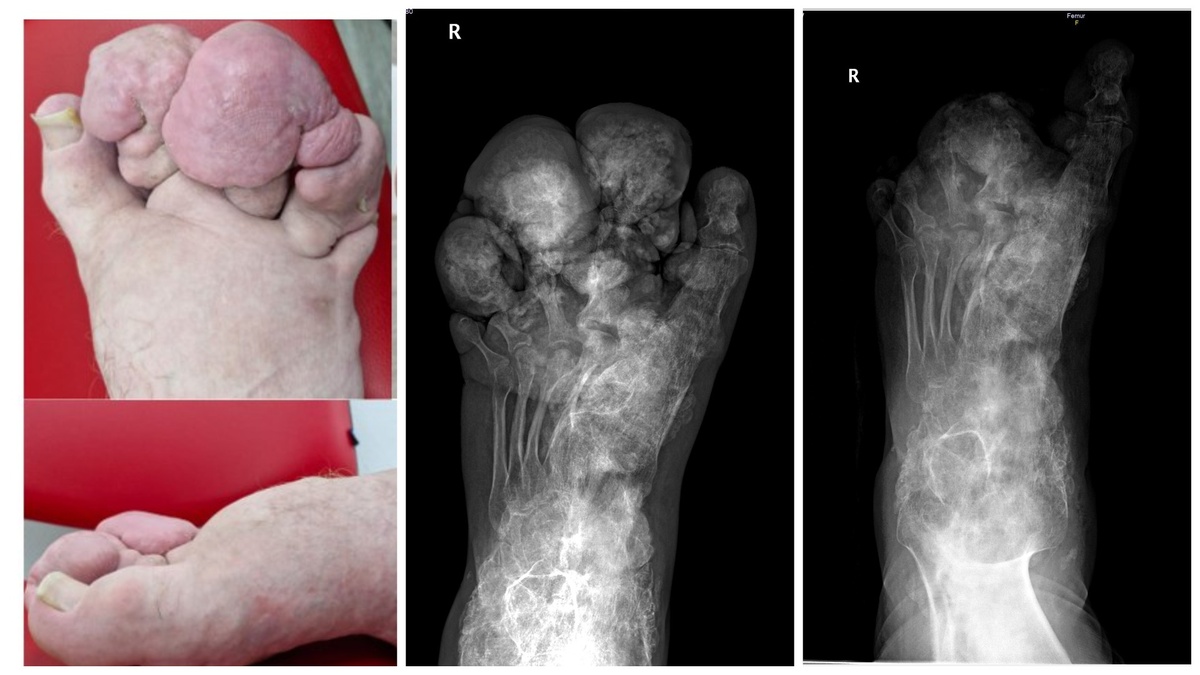

Синдром Протея относится к группе сверхредких врождённых заболеваний. Он встречается с частотой 1 случай на 1 000 000 человек. На фото 1: врач-травматолог-ортопед Игорь Пахомов, фото 2: снимок до операции.

Синдром Протея (название происходит от имени древнегреческого бога моря Протея, который мог изменять форму своего тела), диагностированный Андрею во взрослом возрасте, относится к группе сверхредких врождённых заболеваний. Он встречается с частотой 1 случай на 1 000 000 человек. Наиболее известен случай Джозефа Кэри Меррика — британца, жившего в XIX веке и получившего прозвище «человек-слон» из-за сильной деформации тела, вызванной нейрофиброматозом первого типа и синдромом Протея.

В мировой научной литературе описано всего несколько сотен клинических случаев этого заболевания. Впервые синдром был описан в 1980-х годах американским врачом-исследователем Майклом Коэном. Заболевание характеризуется резким несимметричным ростом, а также чрезмерным разрастанием кожи, костей, мышц, жировой ткани и сосудов. У пациентов деформируются конечности, появляются костные наросты, причём поражаться могут разные части тела.

При рождении, как правило, нет очевидных признаков заболевания. Природа синдрома — генетическая. Согласно научным исследованиям, в результате мутации гена возникают деформации отдельных частей тела, увеличение длины и объёма конечностей или частей головы, а также могут появляться новообразования. Синдром Протея также считается одной из форм парциального гигантизма.

«Такие люди существовали всегда, но, к сожалению, сотни лет назад им не могли помочь. Сегодня у пациентов даже с тяжёлыми поражениями, вызванными заболеванием, есть хорошие перспективы в плане хирургического лечения. Например, данный пациент обратился к нам за помощью с очень тяжёлой деформацией стопы и голеностопной области. Костные разрастания были настолько значительными, что ему было трудно наступать на ногу из-за сильной боли, вызванной ущемлением мягких тканей между костными наростами.

Коллеги сформировали функциональную стопу, удалили костные разрастания и выполнили замыкание голеностопного сустава, который находился в порочном положении. В 2016 году ему провели моделирующую резекцию концевых фаланг нескольких пальцев», — объясняет доктор медицинских наук, врач-травматолог-ортопед ННИИТО Игорь Пахомов.

На первой операции в НИИТО хирурги удалили объёмные костные наросты и сформировали стопу, близкую к анатомически правильной форме

Операция в ННИИТО прошла 12 марта. В составе хирургической бригады работали травматологи-ортопеды Игорь Пахомов и Сергей Гуди, врач-анестезиолог-реаниматолог Иван Стаценко, операционная медсестра Нина Хромова и медсестра-анестезист Евгения Фролова. Во время операции врачи удалили объёмные костные наросты и сформировали стопу, близкую к анатомически правильной форме.